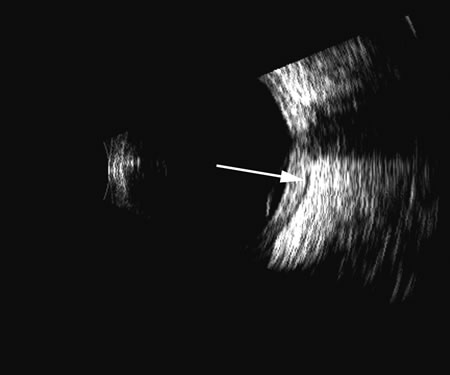

Fig. 4. A clinically well-placed posterior chamber intraocular lens nevertheless had patient complaints of photophobia and irritation due to a folded haptic (arrow).